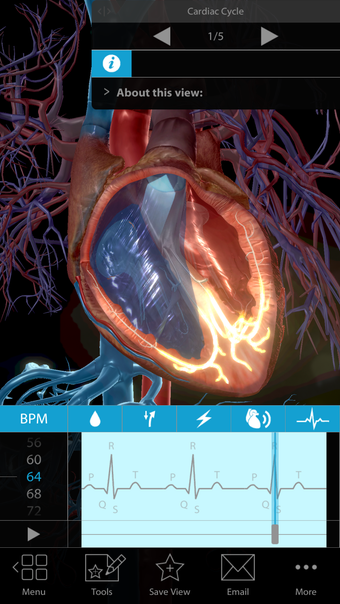

One of the most remarkable features of this application is that it enables users to compare 3D models of normal anatomy with models of common diseases and conditions. Furthermore, users can set the heart rate and visualize conduction in a dissectable, beating 3D heart while following along on an ECG. The application also presents animations that demonstrate the physiological processes of gas exchange, pulmonary ventilation, fluid balance, peristalsis, and more. Interactive lessons walk users through the progression of atherosclerosis, kidney stones, lung cancer, and other common conditions, and quizzes test users' knowledge of various physiological processes and pathologies.